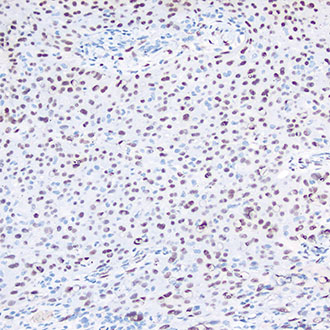

PMS2

PMS2 -